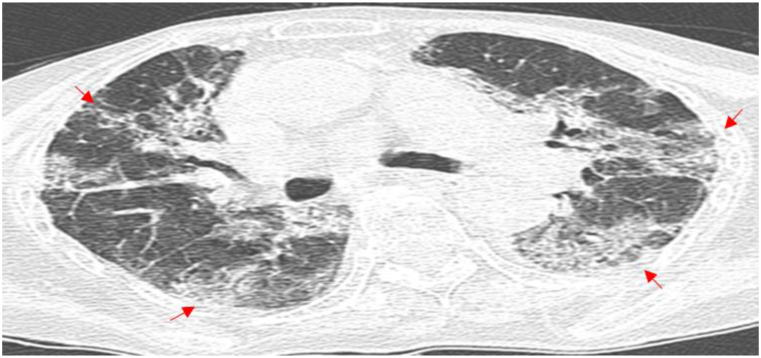

Patient 4 had an underlying condition of coronary atherosclerotic heart disease. Following admission, Patient 4 was treated with moxifloxacin for 2 days, yet without any improvement in the condition. Then, the patient was given an altered therapy of piperacillin-tazobactam combined with levofloxacin for two days. Unfortunately, the patient suddenly developed acute Myocardial infarction and died. After death, the patient was diagnosed with pneumonia caused by TW infection following a discussion by an expert group (Chest CT results in Fig. 5). Patient 5 had underlying conditions of MDS and diabetes. After admission, Patient 5 was initially treated with moxifloxacin for 2 days and subsequently administered piperacillin for 15 days, yet without significant improvement in lung lesions. Subsequently, the treatment plan was modified by the attending physician to long-term treatment with levofloxacin combined with doxycycline, resulting in a gradual improvement in the lung lesions (Fig. 6(a–g)). After a retrospective discussion by the expert group, the patient was confirmed with pneumonia caused by TW infection, and was recommended to be hospitalized to receive the standard treatment plan for WD. However, the patient declined hospitalization, still has a paroxysmal cough at present.

Fig. 5.

Chest CT Scan of Patient 4 (The date is June 6, 2022). The arrowhead shows the focus.